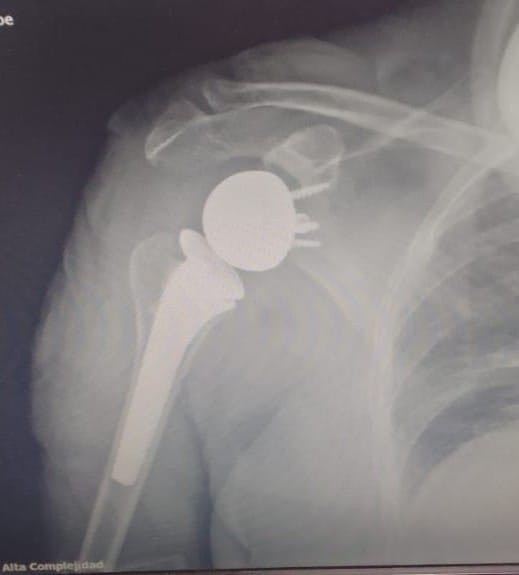

A pocos días de finalizar el 2024, el Hospital de Alta Complejidad “Pte. Juan Domingo Perón”, sigue consolidando su prestigio con importantes logros. Recientemente, el Servicio de Traumatología realizó con éxito la primera cirugía de prótesis reversa de hombro, un avance significativo que reafirma su compromiso con la excelencia médica y la innovación.

Este procedimiento innovador marca un hito en el sistema de salud, permitiendo una mejora significativa en la calidad de vida de pacientes con patologías severas de hombro. La operación fue realizada por la Subespecialidad de Hombro y Codo.

Cabe destacar que, la prótesis reversa de hombro es una técnica avanzada que se utiliza en casos de artropatía por desgarro del manguito rotador o artritis severa, cuando los tratamientos convencionales ya no son efectivos.

Esta cirugía busca devolver la movilidad del hombro utilizando otros músculos prescindiendo del manguito rotador y quitar el dolor.

En este caso la paciente intervenida, de 78 años sufría de una lesión masiva e irreparable de manguito rotador con desgarro y degeneración grasa de los músculos. La misma permaneció solo un día internada y obtuvo su alta médica satisfecha con ejercicios instruidos de movilización del hombro.